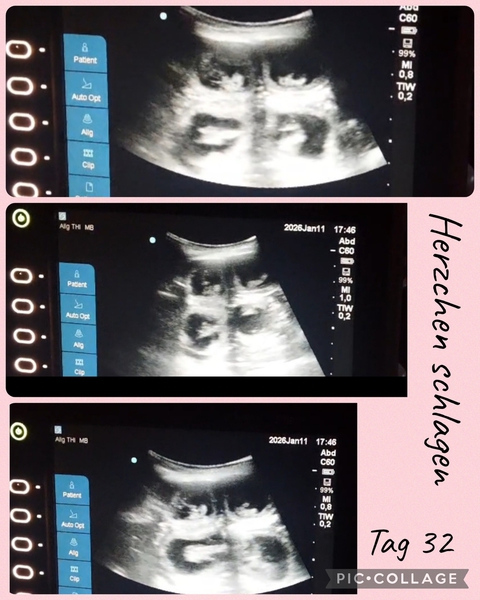

Tragbares Ultraschall

Seid Sonntag sind wir wieder glückliche Besitzer eines Ultraschallgerätes. Ein wunderbares leichtes und auch tragbares US. Durch liebe Menschen hatten wir glück dieses noch nicht so alte Ultraschallgerät zu bekommen. (War vor kurzem noch im Einsatz im KH Notaufnahme). Danke Pelin & Hanno